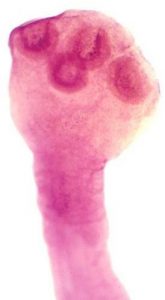

Фото. Личинка свиного цепня (Cysticercus cellulosae): А — Внутри финны находится сколекс паразита и опалесцирующая жидкость. Б — Личинка свиного цепня с вывернутой головкой. В — Сколекс личинки свиного цепня с присосками и хоботком с крючьями.